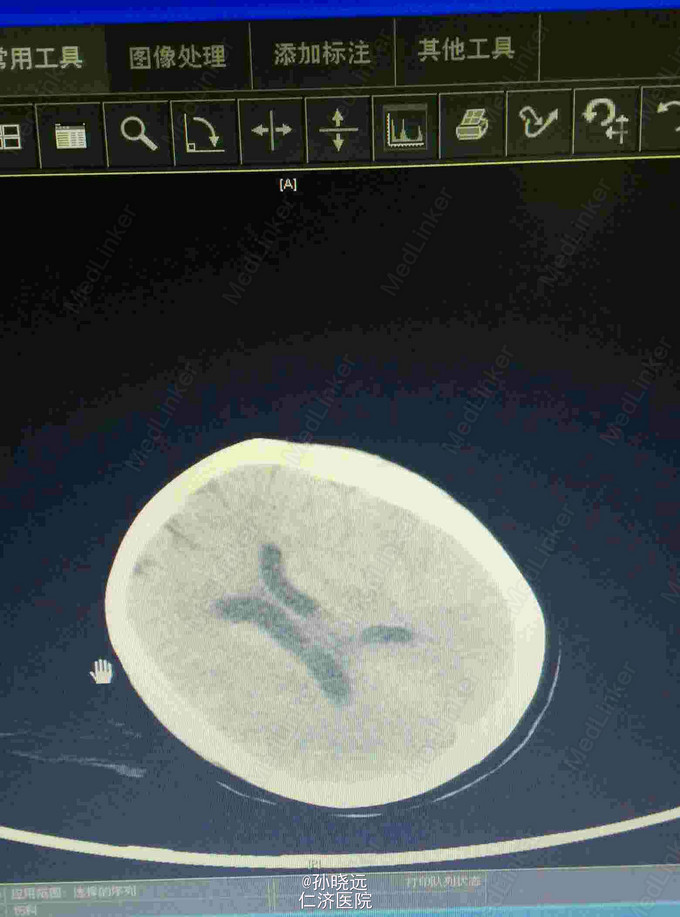

中年女性。主诉:头晕三天,发热伴神志不清1天。 患者于三天前出现持续性头晕,无恶心、呕吐,无视物旋转,来院就诊,查头颅MRI未见异常,予桂哌齐特、长春西汀、硫辛酸治疗,症状无好转。1天前出现高热,最高39.5℃,无咳嗽、气促,再次来院就诊,查血常规:WBC:5.85*10^9/L,N:71.8%,CRP正常,予退热,阿奇霉素等治疗,今日凌晨出现神志不清,无抽搐、恶心、呕吐,头颅CT示两侧颞底部不规则斑点样密度增高影并周围低密度灶,考虑脑炎合并灶性出血,予更昔洛韦、醒脑静、喜炎平、奥美拉唑、甘露醇治疗。后出现氧饱和度下降,予气管插管有创呼吸机辅助通气。 既往史:曾有高血压病史,未应用降压药。

诊断:脑炎。脑出血。 治疗:甲强龙抗炎,更昔洛韦,青霉素钠抗感染,降压,甘露醇、甘油果糖、白蛋白、拖拉塞米里降颅压,呼吸机辅助通气等对症治疗。

腰穿是: 脑脊液生化:葡萄糖:12.18mmol/L,CL:110.9mmol/L,蛋白:222.4mg/dl, 脑脊液常规:淡黄,微混。红细胞:1000*10^6/L,白细胞:1059*10^6/L,潘氏试验阳性(++++),嗜中性粒细胞12%,淋巴细胞:80%,单核细胞8%,凝块无,细菌未找到。 予加用血必净,加强抗感染等治疗。 患者目前仍昏迷,正进行高压氧仓治疗。这是最近一次复查的头颅CT。